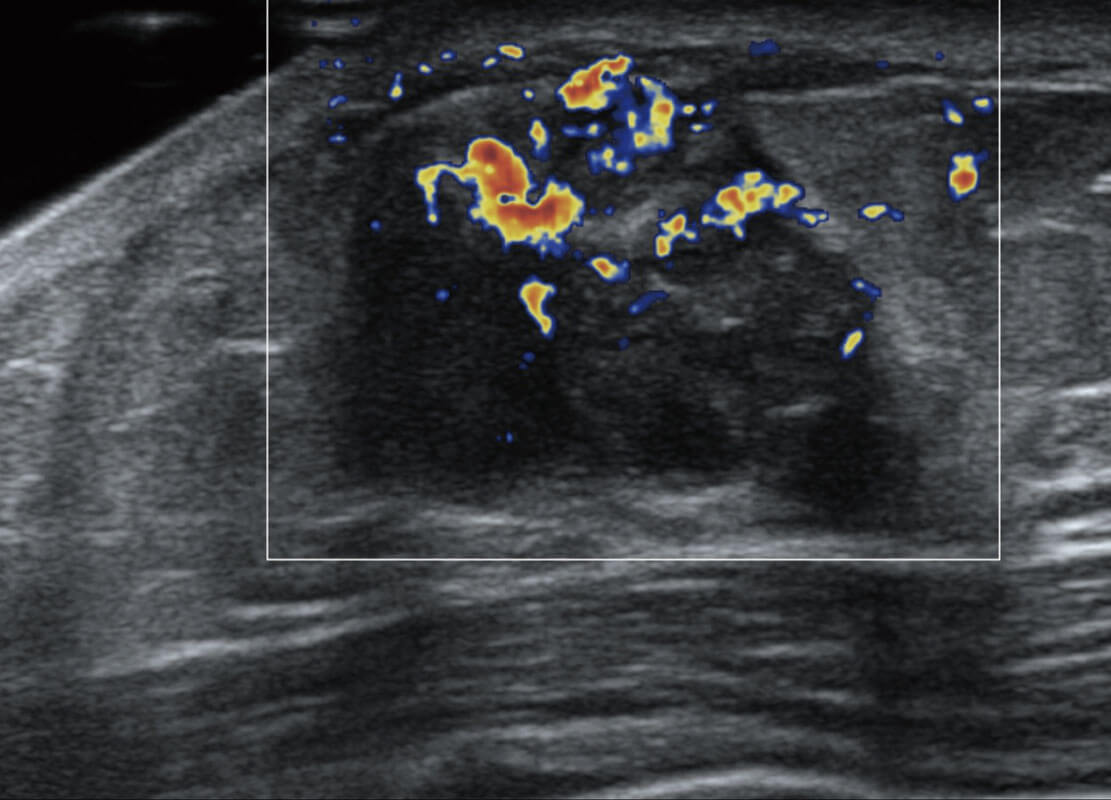

P60搭载宽频带线阵探头、宽景成像、弹性成像技术,为您提供乳腺应用方案。P60支持高频相控阵探头、线阵探头、腹部高频探头、腹部微凸探头等,丰富的探头群搭载敏感的彩色血流成像,适用于新生儿多种脏器检测要求,满足新生儿筛查需求。

乳腺癌显微血流